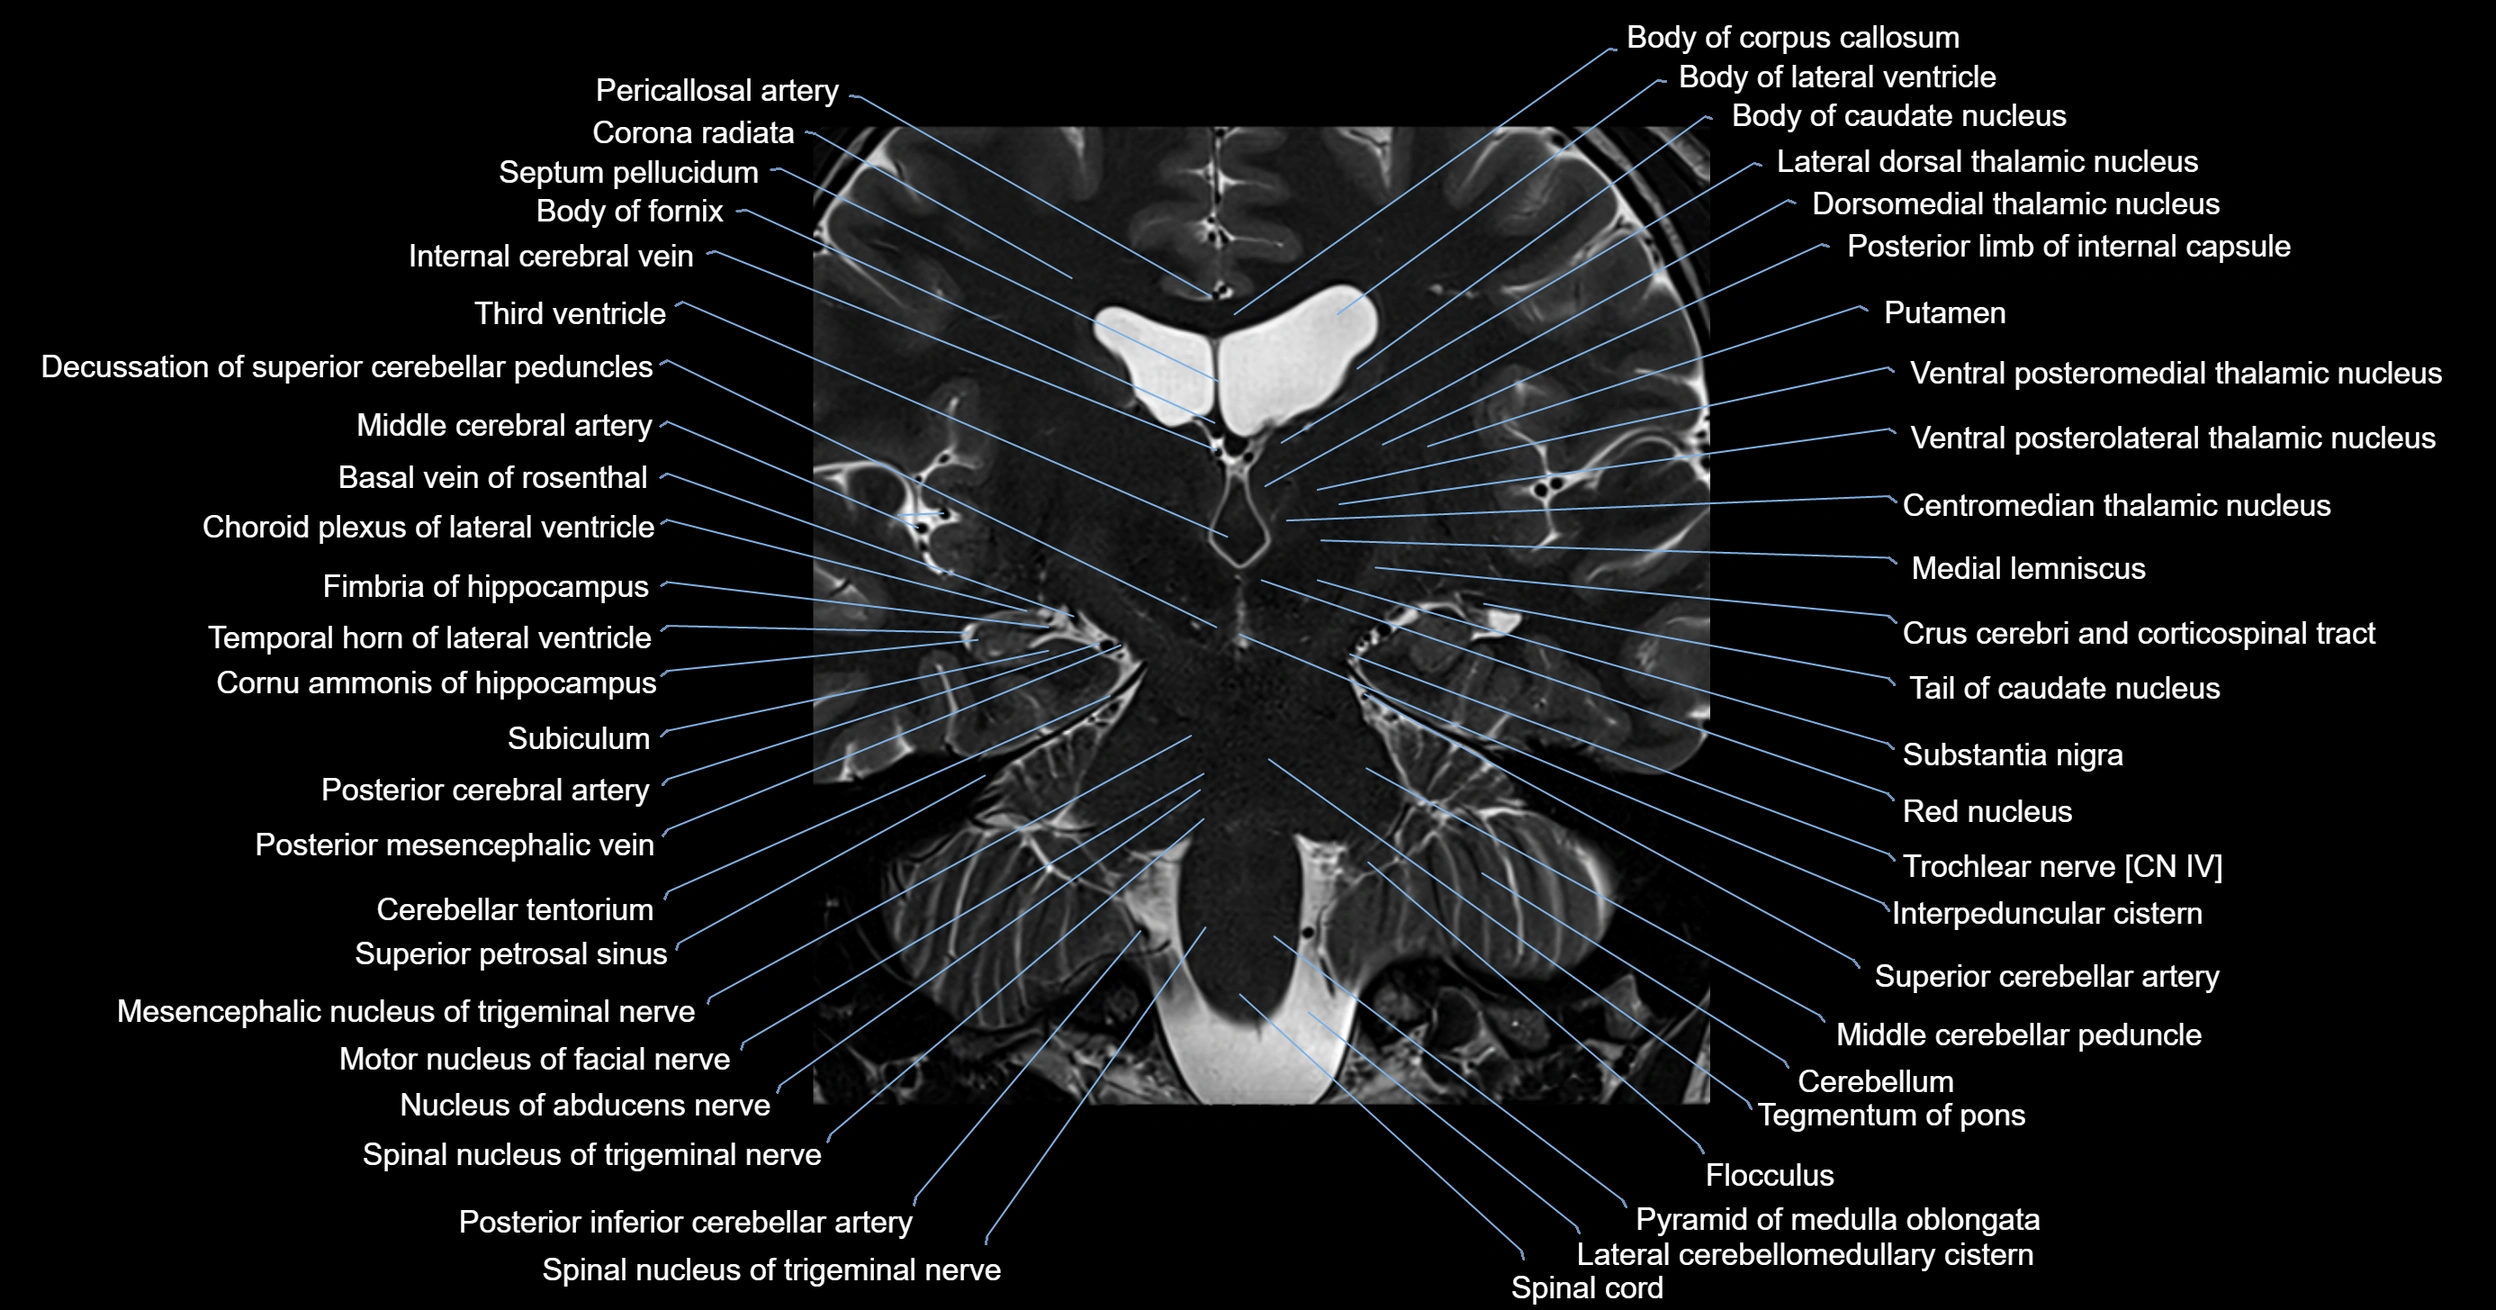

- Body of fornix

- Body of lateral ventricle

- Body of caudate nucleus

- Corona radiata

- Crus cerebri

- Decussation of the superior cerebellar peduncles

- Flocculus

- Inferior cerebellar peduncle

- Internal cerebral vein

- Medial lemniscus

- Middle cerebellar peduncle

- Middle cerebral artery

- Motor nucleus of facial nerve

- Nucleus of abducens nerve

- Pons

- Posterior limb of internal capsule

- Putamen

- Red nucleus

- Spinal cord

- Spinal nucleus of trigeminal nerve

- Substantia nigra

- Superior cerebellar peduncle

- Superior petrosal sinus

- Tegmentum of midbrain

- Tegmentum of pons

- Temporal horn of lateral ventricle

- Third ventricle